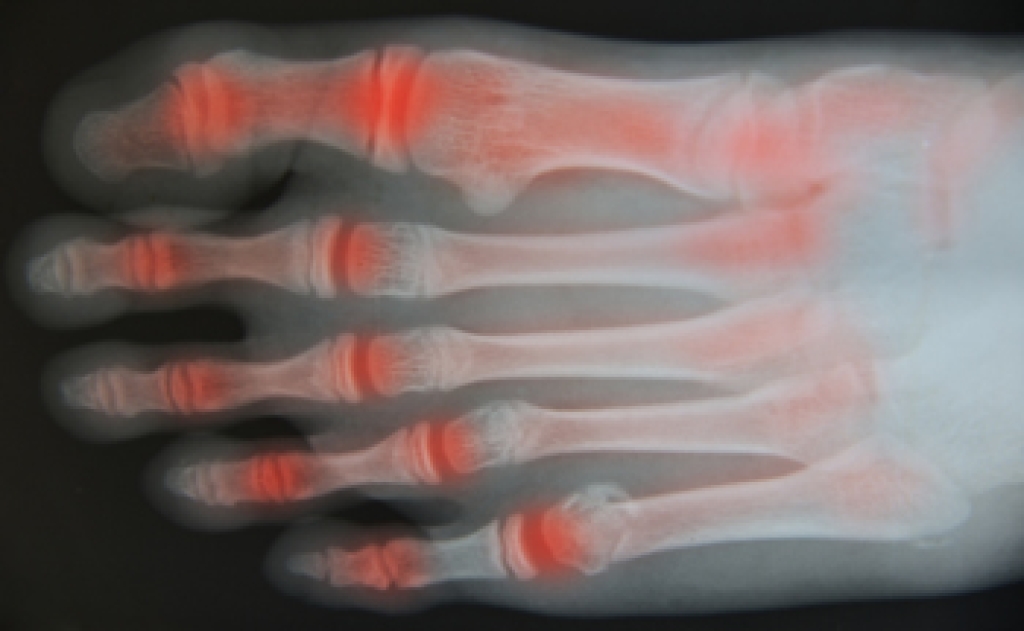

A bone that extends on the side of the big toe is referred to as a bunion. A common reason for this condition to develop can come from wearing shoes that do not provide adequate room for the toes to move freely in. The toes may shift, and one toe may overlap the other. The toes have limited space to move around in, and this may result in cramping. There are other factors that can contribute to the development of bunions, which includes genetics or arthritis. Mild relief may be found when the correct size shoes are worn, and this is helpful in preventing pressure that is put on the bunion. When this condition exists, a diagnosis is performed, which includes having an X-ray, MRI, or ultrasound taken. If you have developed a bunion, it is strongly suggested that you seek the counsel of a podiatrist who can properly treat this ailment.

In order to diagnose your bunion, your podiatrist may ask about your medical history, symptoms, and general health. Your doctor might also order an x-ray to take a closer look at your feet. Nonsurgical treatment options include orthotics, padding, icing, changes in footwear, and medication. If nonsurgical treatments don’t alleviate your bunion pain, surgery may be necessary.